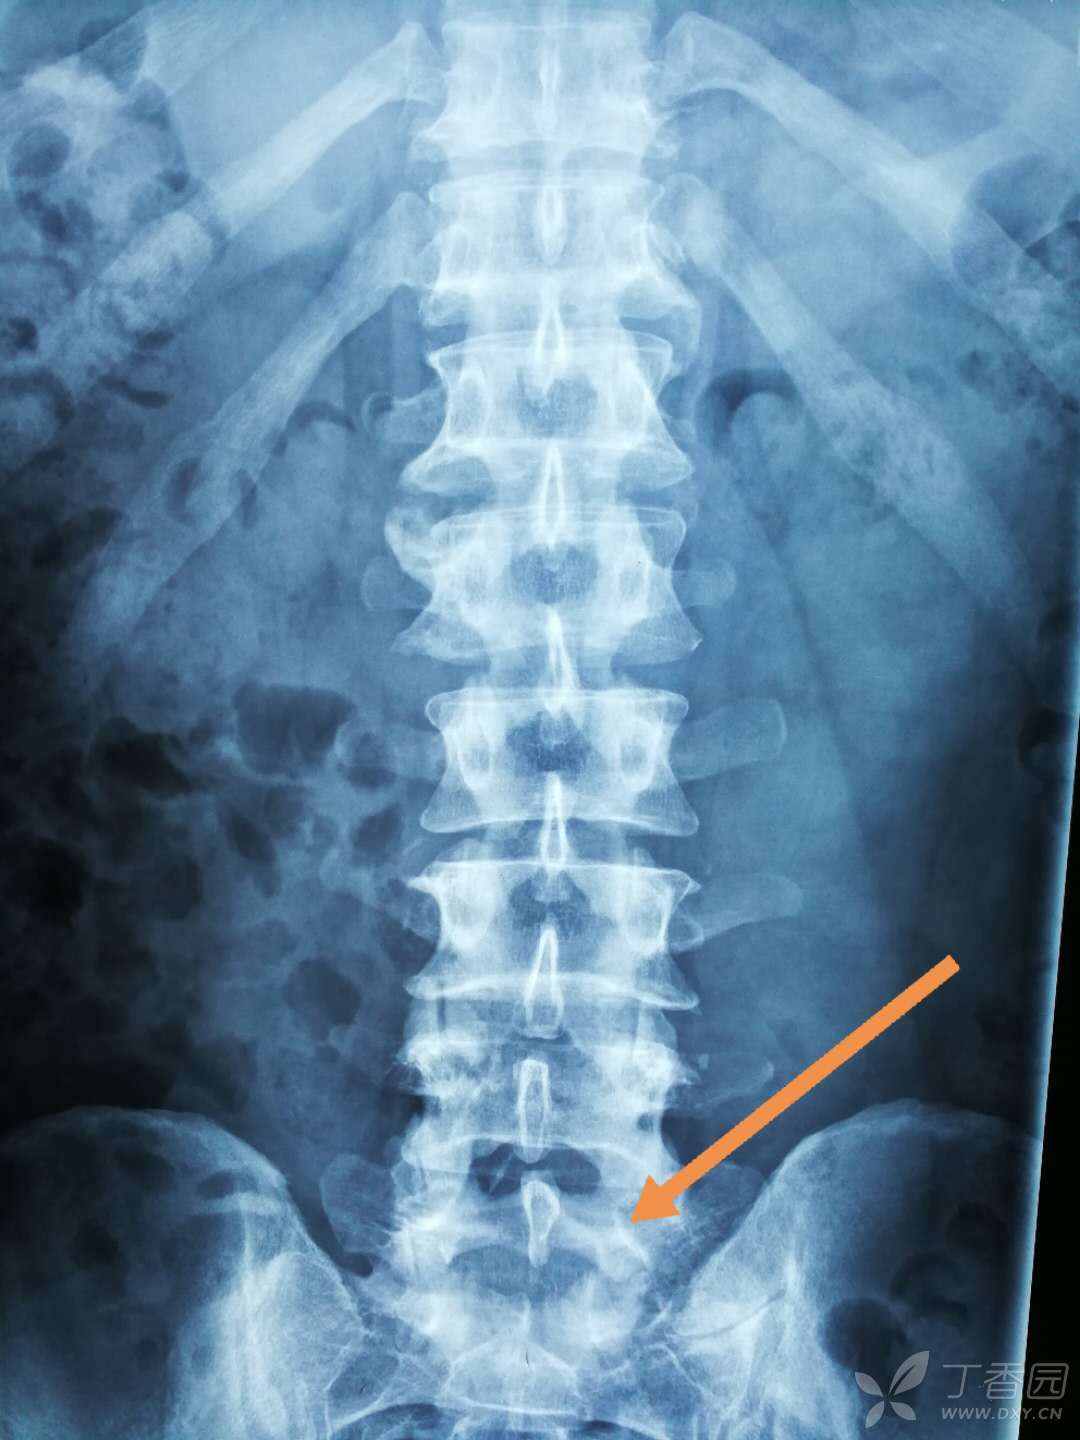

骶椎x线图片

骶骨x光片一张请诸位帮忙掌掌眼

这骶椎怎么回事

男性患者47岁因腰骶不适摄片